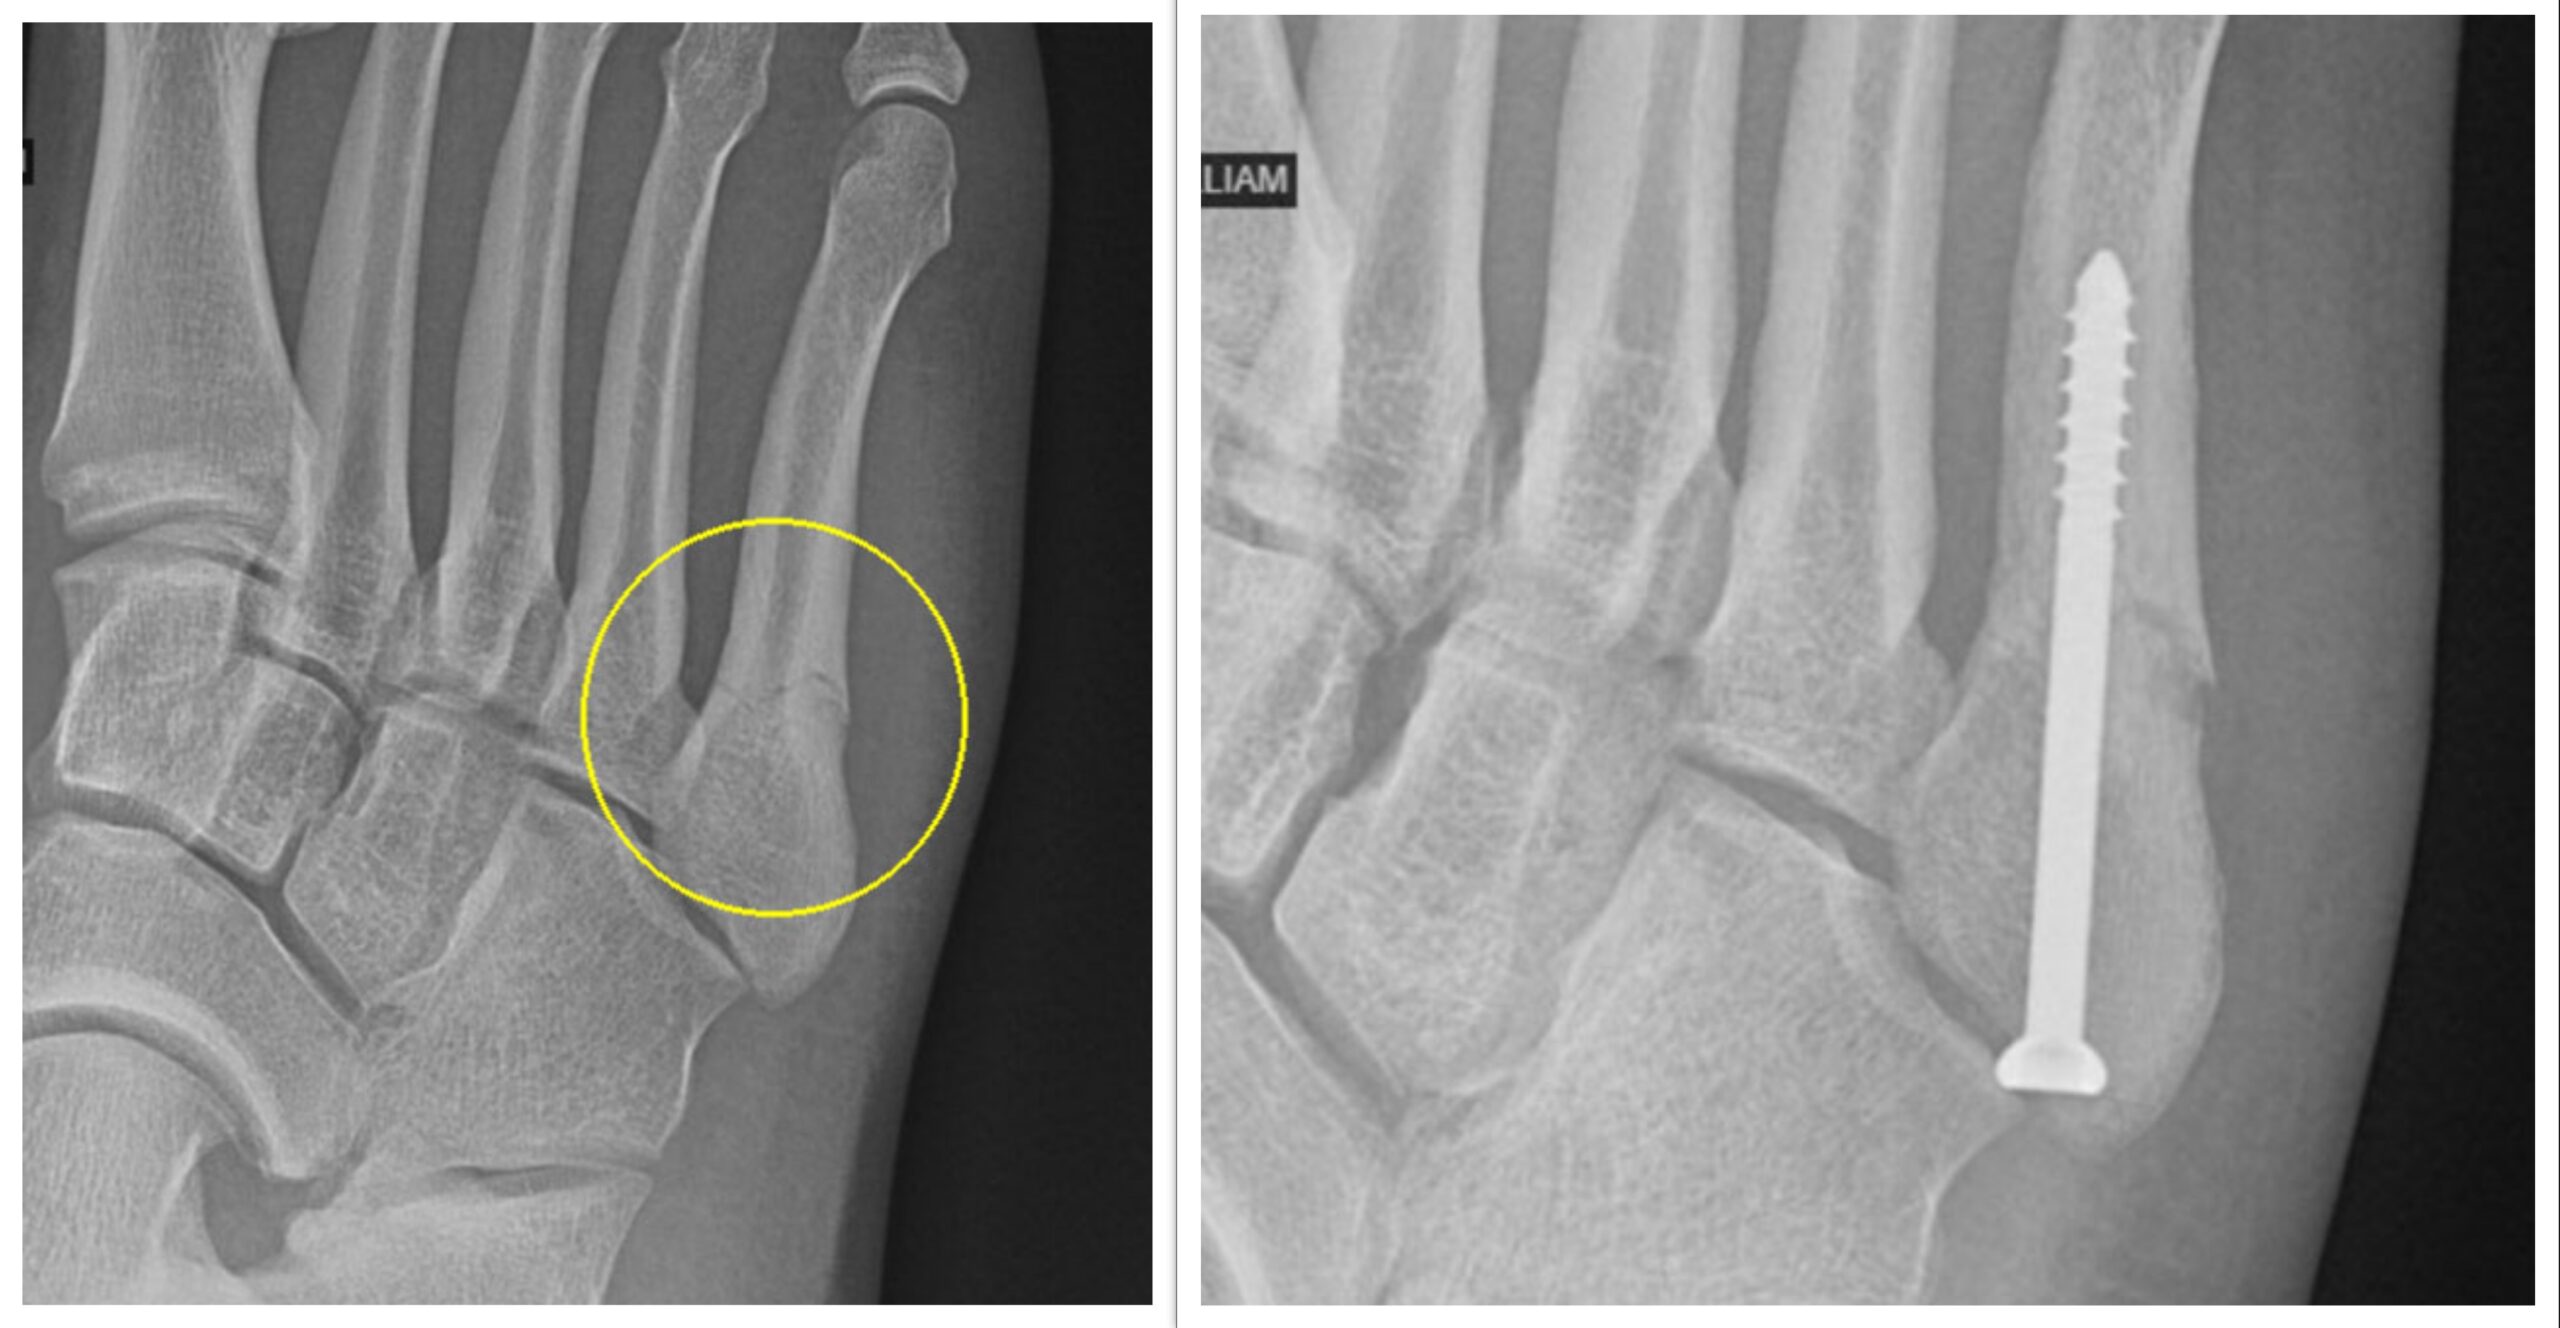

Before-and-after X-rays: The first X-ray shows the break on the outside of Vincent’s foot, and the second was taken 2 weeks after surgery. Dr. Riley surgically placed a screw in the bone to relieve pain, increase stability in the fracture and promote healing.

Dr. Liebig referred Vincent to Patrick Riley, Jr., MD, Akron Children’s pediatric orthopedic surgeon and sports medicine physician. The very next day on Tuesday, Vincent underwent outpatient surgery. Dr. Riley put a 2-inch screw in the middle of the bone to relieve pain, increase stability of the fracture and promote healing to get him back on the field in 6 to 8 weeks.